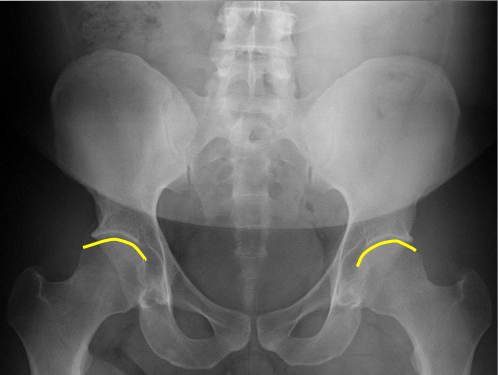

Femur heads

Superior iliac crests

Lateral iliac crests

Ischial tuberosities

Obturator foramen

S2 tubercle

Pubic symphysis

Sacral groove

Lateral aspect of sacrum

Medial aspect of ilium